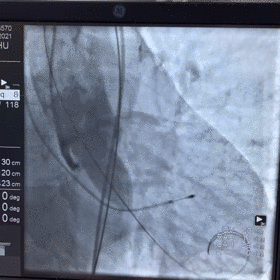

主动脉CT

图片

手术策略

难点分析:

*患者为TYPE0型二叶瓣,重度钙化(钙化积分高达1056),可见钙化延伸至左室流出道,瓣叶前交界缘存在粘连,瓣膜释放后发生瓣周漏的风险较高。

*患者为风湿性心脏病患者,瓣膜释放后移位风险增加,对术者瓣膜植入位置的操控要求较高。

制定策略:

经分析研判,拟从右侧股动脉穿刺入路,使用18mm球囊预扩,采取downsize手术策略,选用L23号的VenusA-Valve瓣膜,因患者伴有风湿性心脏病,瓣膜容易移位,故采用VenusA-Plus可回收输送系统确保瓣膜的稳定释放,瓣膜释放后结合造影和超声情况,决定是否后扩。